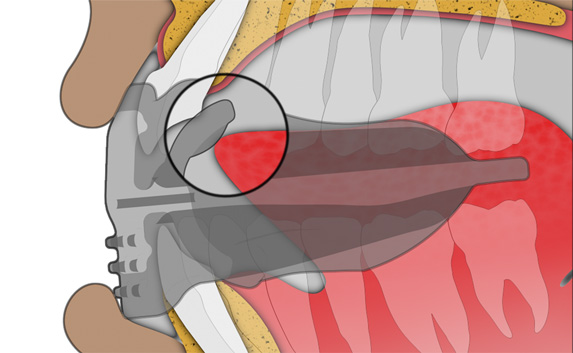

Establish nasal breathing and correct TMJ function

The Myosa® for TMJBDS® S3 is used in the third and final stage of treatment, when the patient's Breath Hold Time (BHT) has reached 45 seconds or more. The S3 is primarily designed to finalise the establishment of nasal breathing, while improving breathing and myofunctional disorders. The S3 can also serve as a transition appliance between the first and second phase of TMJBDS® treatment, involving arch development in combination with the Myobrace® appliances. It is for this reason that the S3 is a derivative of the Myobrace®A1 appliance.